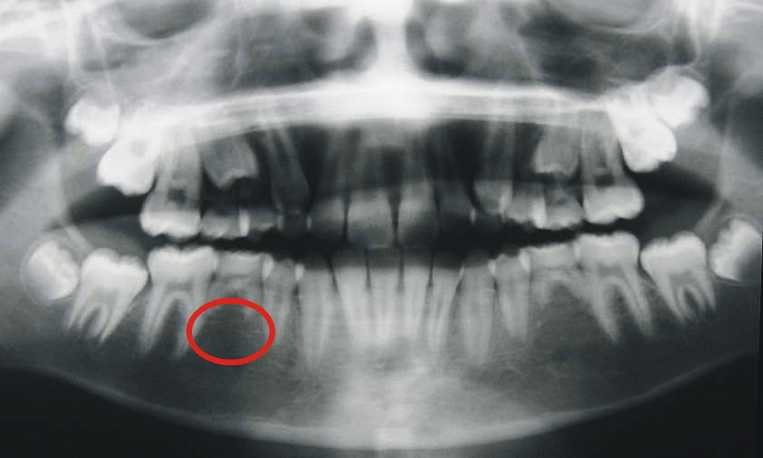

• Rất nhiều bậc phụ huynh đợi cho trẻ thay răng hết rồi mới bắt đầu cho trẻ đi chỉnh răng. Điều này là không đúng. Vì sao vậy ? 1. Một số răng vĩnh viễn lớn hơn răng sữa mà chúng thay thế. Khi điều trị bằng mắc cài giúp cho khoảng mọc răng rộng hơn,răng vĩnh viễn mọc đúng vị trí hơn. Ví dụ như răng nanh hàm trên.Nếu không đủ chỗ mọc,nó sẽ mọc vào vị trí sai lệch,còn được gọi là răng khểnh. Trong trường hợp răng chen chúc,răng nanh sẽ mọc về hướng khẩu cái. Nhưng lợi/vùng khẩu cái rất dày,răng không tự chui ra được và trờ thành răng ngầm. Trong khi nếu đeo mắc cài trước sớm đó,thì sẽ tạo được khoảng quanh răng sữa và tạo được chỗ cho răng mọc.